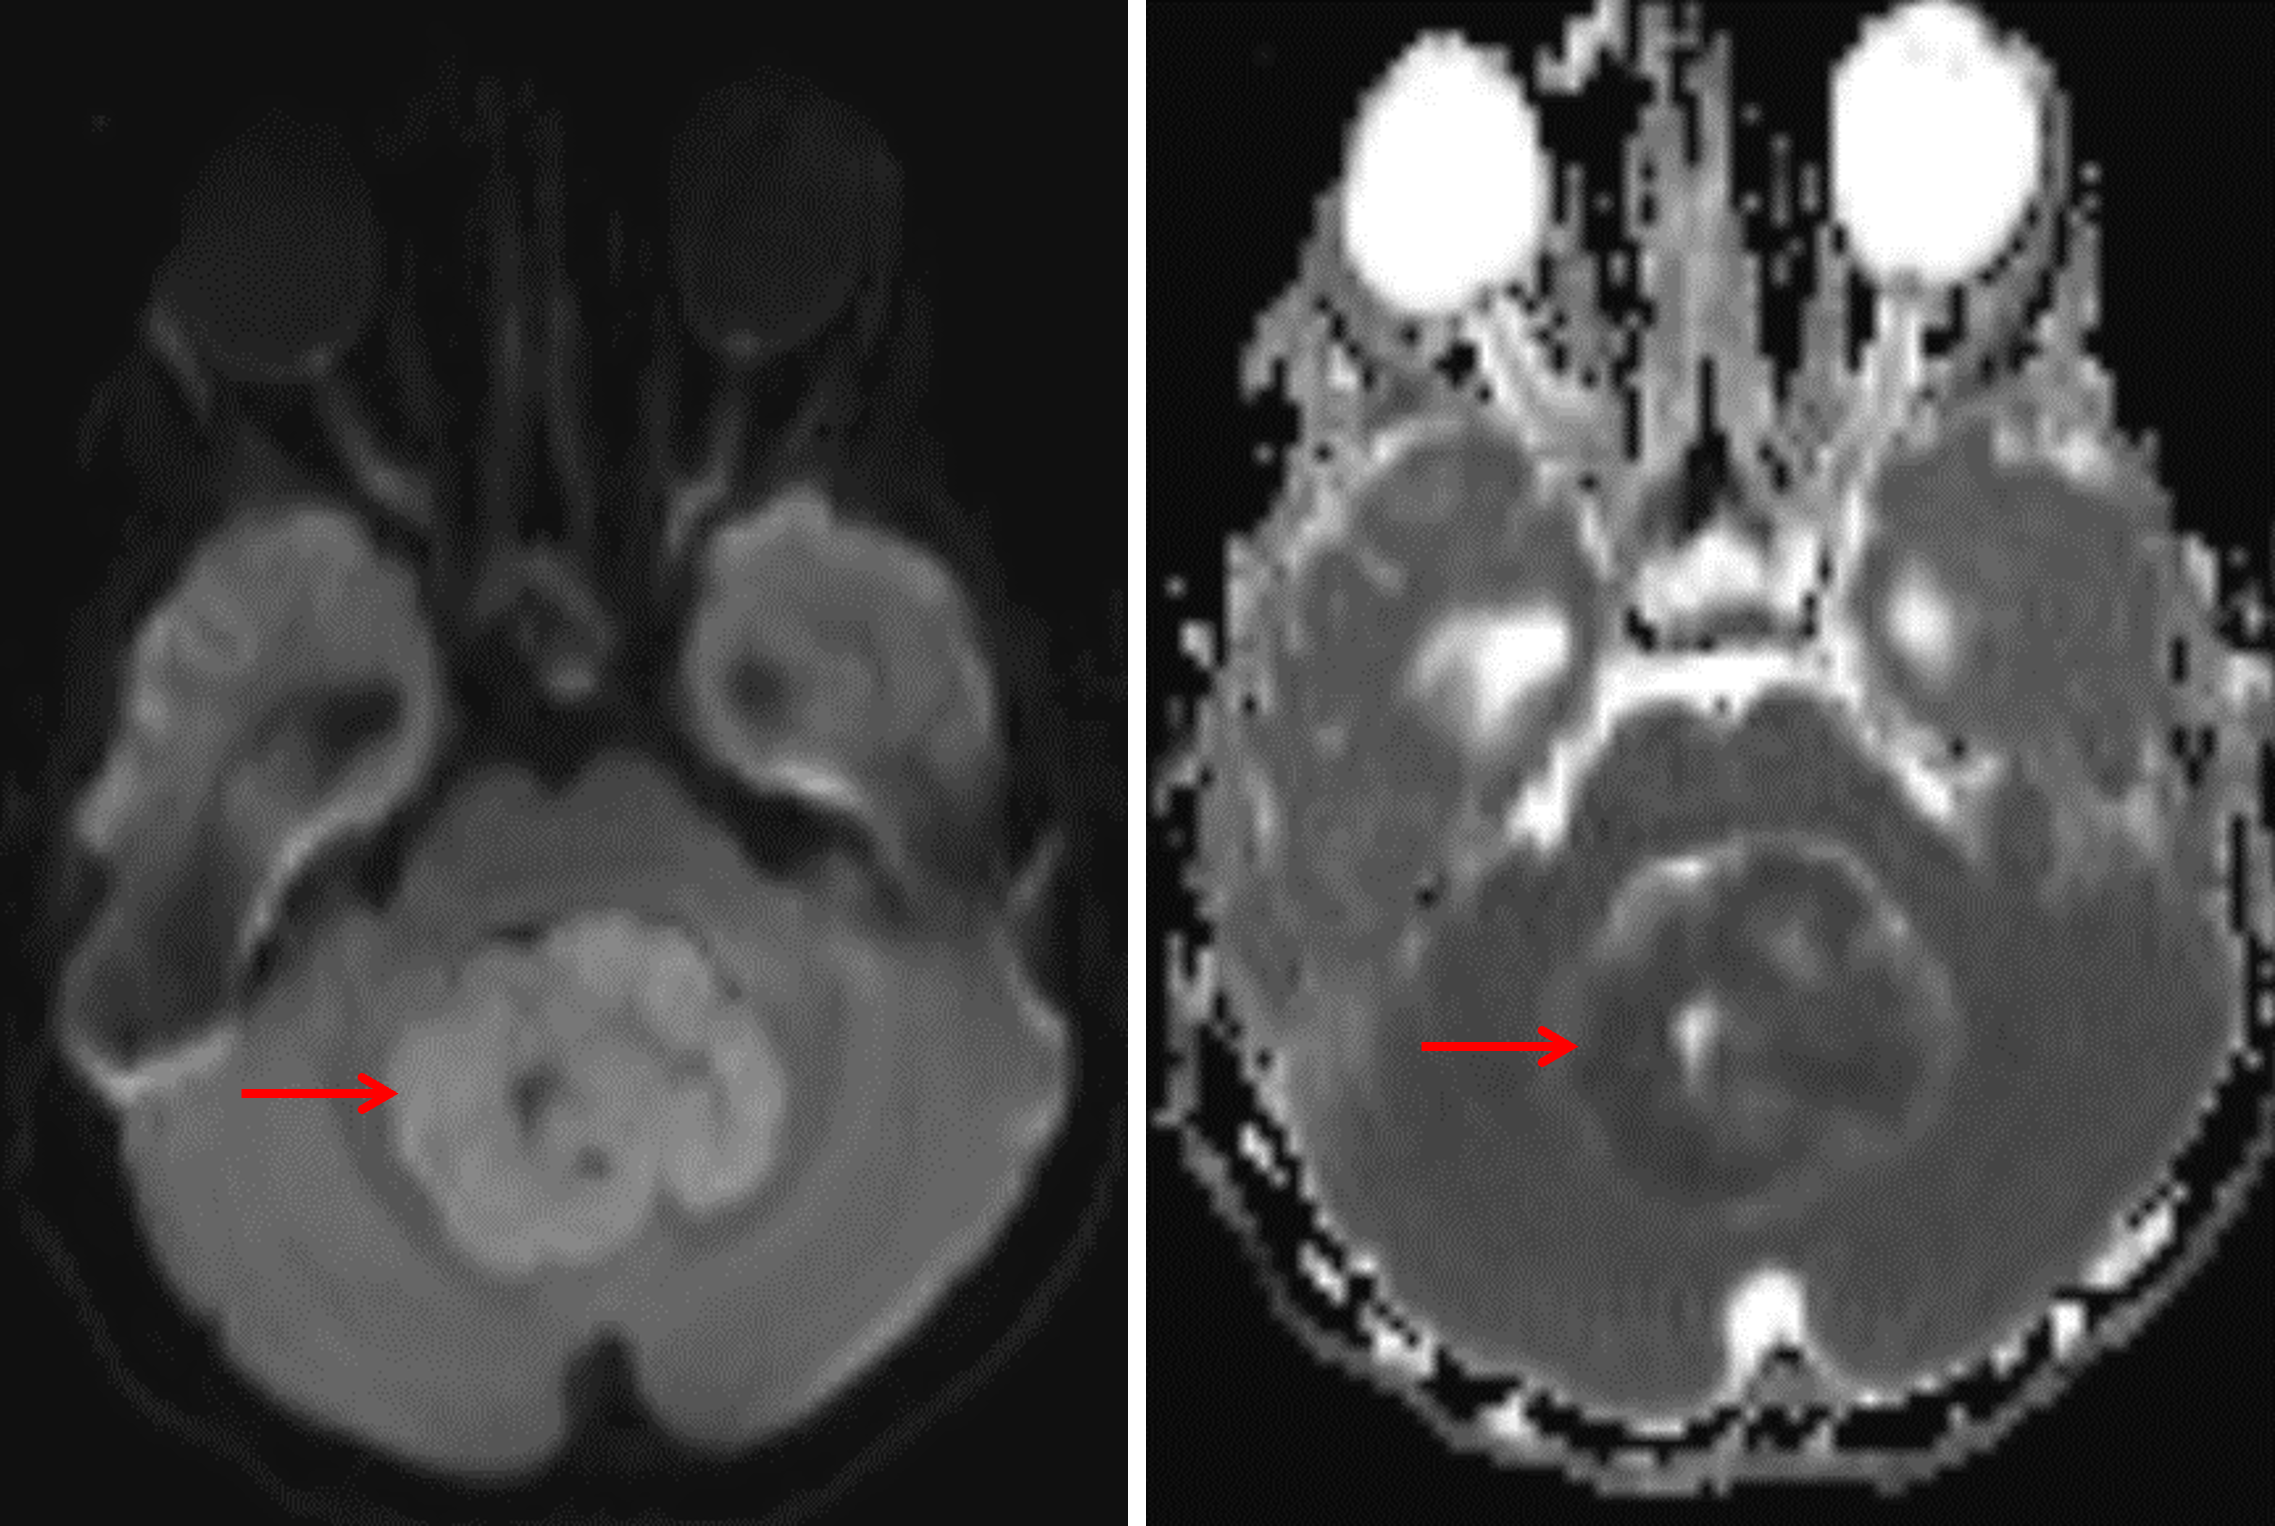

Age: 6

Sex: Female

Indication: Headache

Medulloblastoma